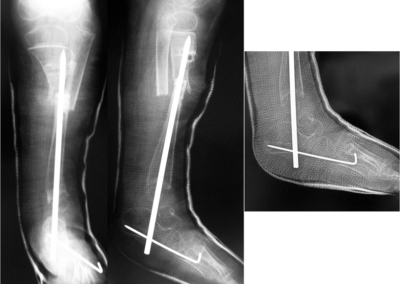

Congenital Pediatric Orthopedic DiseasesDec 30, 2021 | Case ExamplesBilateral GKD Case 1 Bilateral GKD Case 2 Bilateral GKD Case 3 Bilateral GKD Case 4 Congenital Clubfoot Fibuler Hemimeli Tibial Hemimeli PFFD